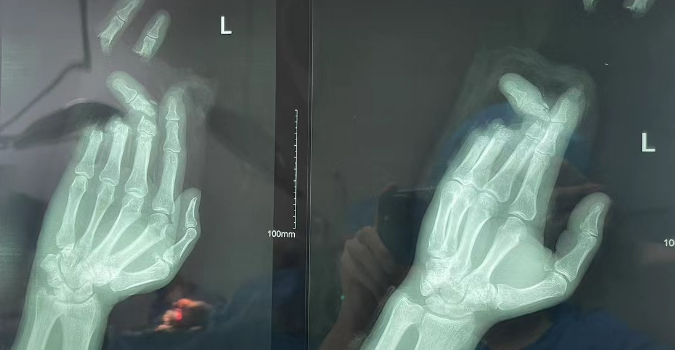

在学术研究方面,李龙飞医生成果斐然。他的论文《锁骨远端骨折合并胸锁关节脱位1例》发表于权威期刊《实用手外科杂志》,该论文以深入的研究、严谨的论证,为骨科临床实践提供了宝贵的参考,并荣获2022年度国家级论文奖。这一成就彰显了他在学术研究领域的卓越造诣。